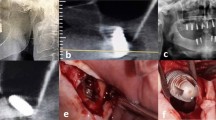

The PliENT endoscope is 370 mm long. Its shaft has a diameter of 2.3 mm and the handle, a diameter of 22 mm. The PliENT endoscope is, as far as the author is aware of, the most slender active flexible endoscope ever made for maxillary sinus surgery (Fig. 2). It’s assembly and control is detailed in the method section. The Supplementary Video V1 online shows the actuation of the PliENT endoscope.

Flexible endoscope for maxillary sinus inspection. (a), view of the bending capabilities of the 2.3 mm diameter endoscope; (b), detail of the endoscope distal tip with camera and illumination; (c), overview of the different components of the single-handed, flexible, steerable endoscope for maxillary sinus surgery. 1. tip; 2. NiTi shaft; 3. cable ; 4. screw-on cap; 5. two-parts-handle; 6. button interface; 7. mobile outer tube of the concentric muscle; 8. fixed inner tube of the concentric muscle; 9. McKibben muscle; 10. plug-on cap; 11. pressure source connector; 12. pressure source tube; 13. chip-on-tip camera; 14. light fiber.

Instrument assembly

The PliENT endoscope for maxillary sinus surgery is intended to be disposable. It has a cylindrical handle of 22 mm outer diameter. The handle is 3D printed using a Vero white RGD835 material and is made of two parts (parts 5 in Fig. 2c). Both parts of the handle fit together one upon another and are fixed using a plug-on cap proximally and a screw-on cap distally (components 10 and 4 in Fig. 2c, respectively).

On the upper portion of the handle, two push buttons are embedded for commanding the embedded actuators that steer the flexible distal tip. The buttons are obtained by cutting and modifying an Adafruit keypad (Adafruit Industries, New York, USA) from a 1 × 4 towards a 1 × 2 formfactor. As such, it fits the user interface frame integrated in the handle (part 6 in Fig. 2c). In order to make the endoscope actuation intuitive for the surgeons, the interface was placed in line with the bending plane of the distal part. The surgeon therefore knows that the bending direction is aligned with the longitudinal symmetry plane of the keypad.

Inside the handle, a 6 mm diameter McKibben pneumatic artificial muscle with integrated channel, introduced by our group in earlier work36, is used as linear actuator for bending the distal tip (part 9 in Fig. 2c). A McKibben artificial muscle is a linear actuator operated by pressurized air. It is composed of an internal bladder reinforced by a non-extensible braided mesh. The internal bladder is connected to an air supply37. By increasing the air pressure, the bladder tends to expand radially. Since the braid length is constant, the braid angle increases and the actuator contracts. The Supplementary Video V1 online shows the basic principle of a McKibben artificial muscle. The McKibben artificial muscle is here chosen as actuator because of its miniaturization potential, large power density and operational bandwidth and compliant behaviour, which offers safety to the patient37. The muscle is slid onto and fixed at one end to a mobile stainless-steel outer tube with an external diameter of 1.8 mm and a wall thickness of 0.1 mm, and at its other end to fixed stainless-steel inner tube of 1.5 mm external diameter and 0.1 mm wall thickness (parts 7 and 8 in Fig. 2c). This system of two tubes surrounded by a muscle was introduced under the name: concentric muscle36. The fixed inner tube acts as a working channel where the camera and light source can be inserted. In order to ensure the muscle fixation, a conical ring is slid onto the muscle at the level of the attachment inside the handle. The whole muscle fixation is secured by adding a small quantity of epoxy glue (Loctite EA 3430, Düsseldorf, Germany).

In the handle, at the level of the muscle attachment, a duct has been created that serves as a connection to an air supply that drives the muscle. Proximally, a thin tube ensures the connection between the fixed handle-muscle attachment piece and the pressure connector (component 12 in Fig. 2c). The pressure connector, a QSM mini Festo push-in connector (Festo, Esslingen am Neckar, Germany, component 11 in Fig. 2c) ensures easy plug-in of an external pressure source.

Distally, a stainless-steel steer cable of 0.2 mm diameter (Carl Stahl, Süßen, Germany) is welded using silver to the distal part of the mobile outer tube of the McKibben muscle (part 3 in Fig. 2c). This cable is glued to the distal tip using epoxy glue 204-CTH (Dymax Corp, Torrington, USA). The tip is glued as well to the distal end of the NiTi notched tube (2.3 mm inner diameter, 0.15 mm wall thickness and 200 mm long). Latter tube covers the tubes of the concentric McKibben muscle. The NiTi shaft has been heat-treated prior to manufacturing. More specifically, the sample was annealed at 550 °C for 10 mins. This heat treatment allows to decrease the NiTi stress plateau and therefore the load required to bend the NiTi backbone38. The notches were cut into the NiTi shaft using the wire-EDM manufacturing process. The shaft is fixed to the handle using a clamp ring intrinsically printed inside the handle (part 5 in Fig. 2c). The tip of the endoscope is 3D printed using the HTM 140 material. Finally, a NanEye camera (AMS, Premstaetten, Austria) and a light fiber (Dorc, Zuidland, The Netherlands) are inserted inside the distal tip and glued using epoxy (Fig. 2b). The NanEye camera is a relatively cheap chip-on tip camera that was already used in previous studies on surgical instrumentation39,40.

The whole endoscope is 370 mm long and only weights 51 g. Its shaft has a diameter of 2.3 mm and the handle, a diameter of 22 mm. The PliENT endoscope is, to our knowledge, the most slender, active, steerable endoscope ever made for maxillary sinus surgery (Fig. 2a). In order to avoid the insertion of a sensor in the distal tip, which would increase the instrument diameter, a feedforward control scheme was adopted in order to control the distal tip. More specifically, a modified generalized Prandtl–Ishlinski model described in our previous publication was used41. The instrument can bend up to 93° by pushing on the upper button of the interface. The lower button on the interface allows to decrease the instrument bending angle. The maximum bending rate was set to approximately 11° per second. This bending rate is measured when producing a continuous push on the interface button. The system was set to allow more precise control with a short push. Upon a short button push, the instrument would bend 0.3°. This was done to allow small and precise adjustments upon wish. This specific slow rate was chosen for the experiments in order to avoid sudden changes in bending, and allow the surgeon to precisely inspect the maxillary sinus cavity. Note that the bending rate of the instrument can be adapted in order to match the surgeon’s preference.